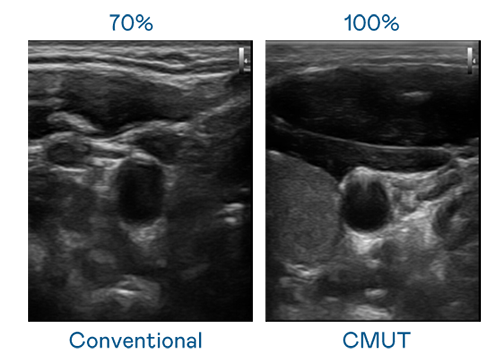

CMUT 技术是一种用电容式微机电元件来产生超音波讯号的技术。与传统 PZT 压电式技术相比,CMUT 频宽增加 30%,更宽频的超音波讯号让影像解析度大幅提升,是实现高影像品质医疗超音波扫描、促进精准医疗发展的关键技术。

大频宽带来超清晰影像

超音波影像的解析度高低,首先取决于探头能发出的讯号频宽。AG亚娱 CMUT 可提供高清晰的超音波讯号,提供高频宽、高灵敏度、影像纹理细节更高的超音波影像,协助医护人员缩短影像判读时间及利用精准的医疗影像进行诊断。